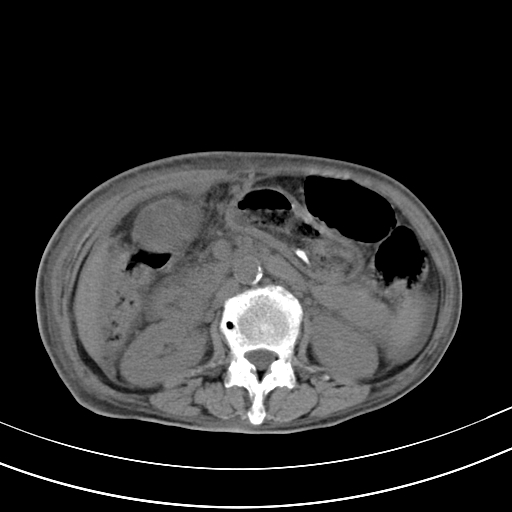

病人上腹部胀痛拌全身黄染八天

结石好象不明显吧?胆管稍扩张。

右侧少量胸水,胆囊增大,肝内胆管扩张,肝门部结构杂乱,建议增强。

肝内胆管及胰管扩张考虑为胰头区占位,肝门淋巴结增多,肝内多发低密度影,考虑为转移。门脉高压,脾大,胆囊大。

肝内胆管及胰管扩张,胰头增大考虑为胰头区占位,肝门淋巴结增多,考虑为转移。建议增强,脾大,胆囊大,壁厚,慢性胆囊炎。胃壁好像也增厚,且有一肿物。

1)考虑胰头癌并胆系低位梗阻;建议行ct增强扫描检查。2)慢性胆囊炎。3)脾大。4)少量腹水。5)双侧少量胸腔积液。